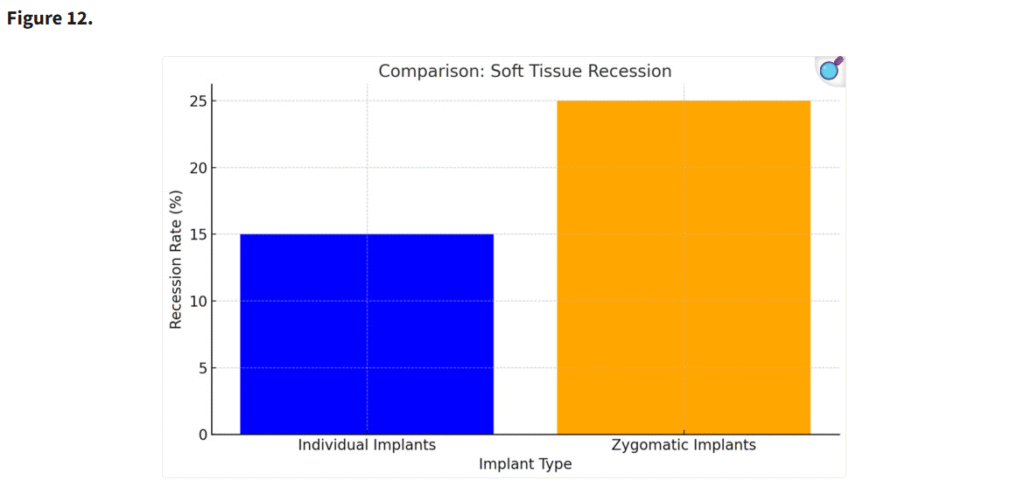

3.4. 軟組織退縮

個別設計インプラントでは、ザイゴマインプラントと比較して軟組織退縮の発生頻度が有意に低かった(p < 0.05)。個別インプラントの精密な設計と埋入位置により、軟組織の統合が向上し、審美的な結果も改善された(Figure 12)。

エクストラマキシラリー法によるザイゴマインプラント埋入は、軟組織裂開のリスクが高い(p < 0.05)。